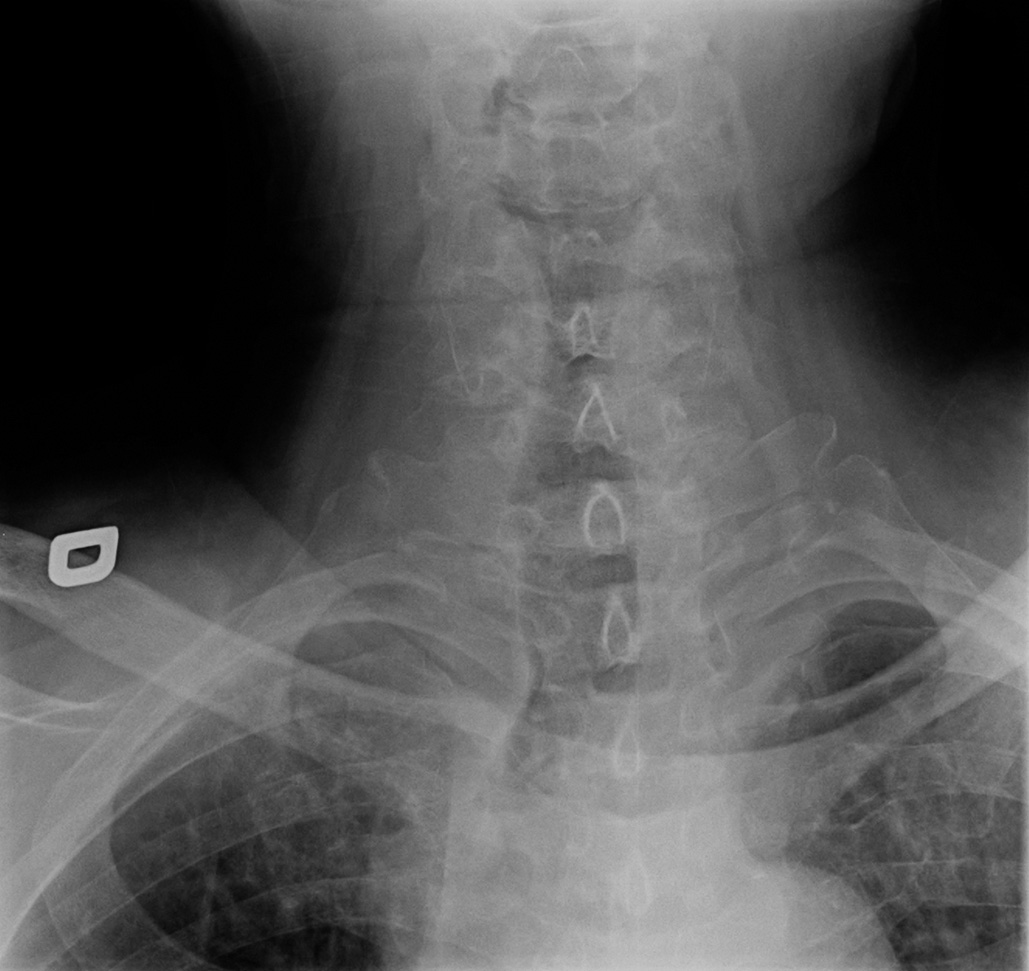

96-year-old female:

Cervical pain following a fall down the stairs.

Odontoid type 3 fracture located slightly below the odontoid waist and involving the body and lateral masses of C2.

Uncodiascarthrosis

Discarthrosis

Bone irregularities

Anteroposterior